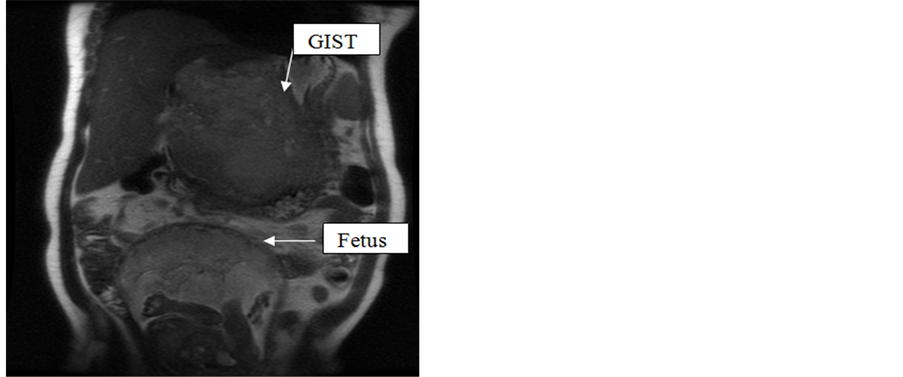

She is a 42-years-old patient, mother of 7 children, in the fifth month of pregnancy. Admitted for treatment of moderate hepatic colic pain, dating back to seven months, atypical epigastric pain, epigastric fullness relieved by post prandial vomiting, associated with fever and general state. Clinical examination found a patient in a good general state, a distended abdomen with uterine height of 18 cm, an epigastric smmoth and painful mass of 10cm. Laboratory tests showed a hypochromic microcytic anemia with a biological inflammatory syndrome. The morphological assessment including abdominal ultrasound has objectified a hepatic cystic and tissue mass, with thickened and irregular contours. Hepatic MRI found a large lesion process in the epigastric region, this lesion is heterogeneous with dual component: a liquefied center (rich in mucin and blood) and very irregular peripheral component with irregular and asymmetric internal contours. This mass is localized in the epigastric region, tacking the left liver and coming into contact with the stomach wall (small curvature) (Figure 1, Figure 2).

Figure 1. Axial view of the stromal tumor in MRI.

Figure 2. Sagittal view of the stromal tumor in MRI.